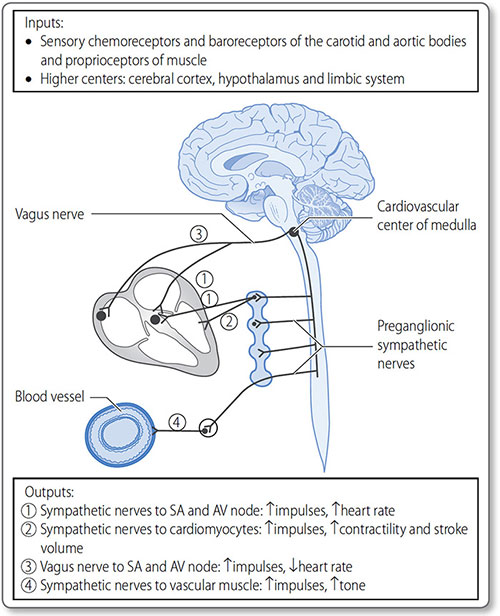

Autonomic control of the heart

The cardiovascular center is a collection of nuclei in the medulla oblongata, and is the branch of the ANS responsible for cardiovascular homeostasis and control. It receives sensory input from peripheral chemo- and baroreceptors, and higher control from the thalamus, hypothalamus and cerebral cortex (Figure 1.28). Through its modulated output it regulates:

- Heart rate (see page 47)

- Cardiomyocyte contractility (see page 46)

- Global blood flow (see page 49)

- Blood pressure (see page 58).

The sympathetic nervous system

Sympathetic signals are transmitted from pre-ganglionic neurons in the lateral thoracic and lumbar spinal cord (levels T1–L2). These synapse with post-ganglionic neurons within the right and left paravertebral ganglia (the sympathetic chains).

Sympathetic nerves innervate the atrial and ventricular myocardium, SA node, AV node and conduction tissues. They release noradrenaline (norepinephrine), which – along with adrenaline (epinephrine) in the bloodstream – activates β1 adrenoreceptors in the heart.

Effects

Activation increases intracellular cyclic AMP (cAMP) and protein kinase A activation, causing changes in ion channel gating (Table 1.10), and thereby increases:

- Heart rate, i.e. chronotropicity

- Contractility, i.e. inotropicity

- Myocardial relaxation, i.e. lusitropicity

- Conduction through the AV node, i.e. dromotropicity.

Figure 1.28: The cardiovascular center of the medulla is responsible for the global control of heart rate, contractility and stroke volume, as well as vascular tone, the core determinant of blood pressure.

The parasympathetic nervous system

Efferent parasympathetic innervation of the heart is through the right and left vagus nerves (cranial nerve X), which originate in the nucleus ambiguous of the medulla oblongata. Pre- and post-ganglionic neurons synapse very close to the heart. Post-ganglionic neurons primarily innervate the atrial myocardium, SA node and AV node.

|

Vagal activation releases acetylcholine, which binds to muscarinic M2 receptors, antagonizing cAMP production and protein kinase A activation. Vagal activation also results in K+ channel activation and hyperpolarization of the myocyte membrane.

The parasympathetic nervous system reduces heart rate by reducing pacemaker potentials.